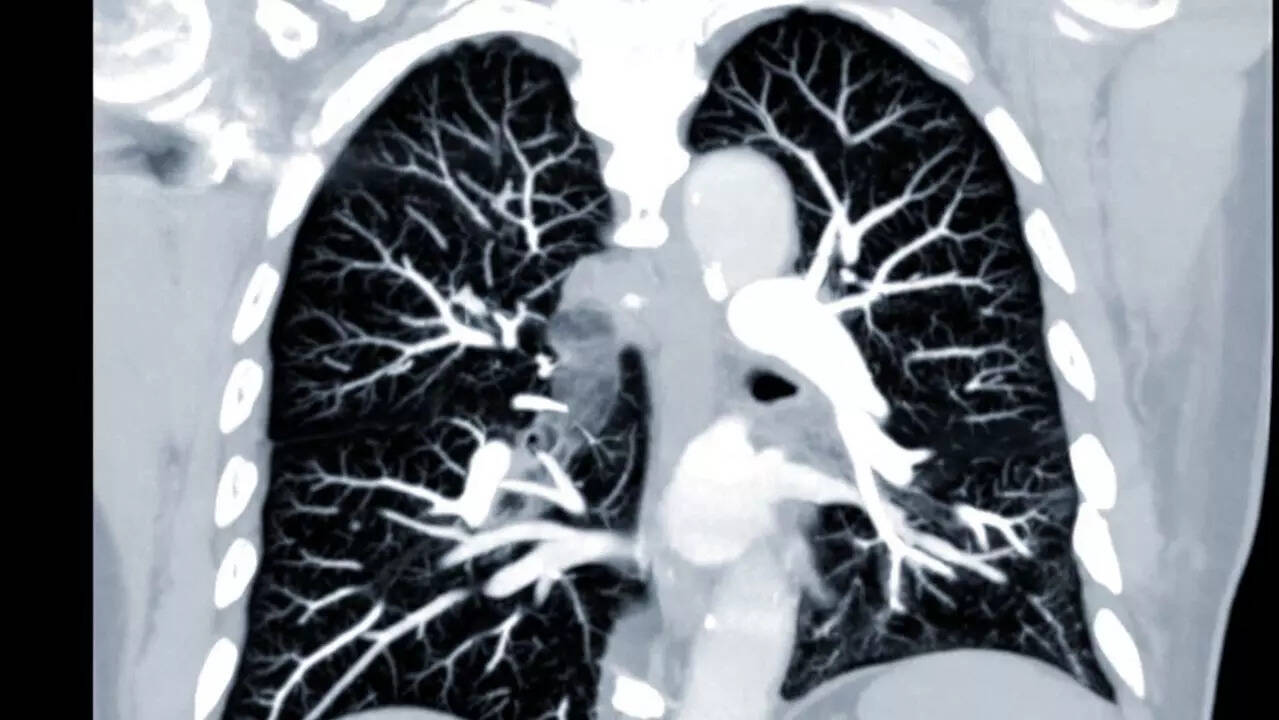

A new study has uncovered significant lung abnormalities in children and teens suffering from long Covid using an advanced MRI technique known as PREFUL MRI that doesn’t require radiation or contrast dyes. The findings were published in the Journal Radiology.

Children and teens with long Covid have significant lung abnormalities detected with an advanced form of magnetic resonance imaging (MRI), called free-breathing phase-resolved functional lung (PREFUL) MRI. The findings were published yesterday in Radiology.

PREFUL MRI is short for free-breathing phase-resolved functional lung MRI. Unlike traditional imaging, PREFUL MRI allows doctors to scan the lungs while children simply breathe normally. Also, it’s entirely radiation-free and doesn’t require any contrast dye, which makes the technique safer for young patients.

For the study, a total of 54 participants - 27 with long Covid and 27 without it, underwent PREFUL from April 2022 to April 2023. Half of the participants had long Covid, while the other half had no history of the condition. The average age was 15 years old. The imaging assessed regional ventilation (oxygen flow), flow-volume loop correlation metric (FVL-CM), quantified perfusion (blood flow), ventilation and perfusion defect percentages, and ventilation-perfusion ratios.

The findings of the studyThe scans revealed that children and teens with long Covid showed clear signs of lung injury, the damage that was invisible on standard tests. Their lungs had reduced blood flow (perfusion), and there were ventilation-perfusion mismatches, meaning areas of the lung weren’t properly balancing airflow and blood flow.